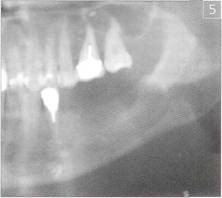

На контрольной рентгенограмме, сделаной через 1 месяц после операции, костный дефект выполнен трабекулами, наметились контуры нижнечелюстного канала (рис. 4), что свидетельствует о наличии молодой костной ткани. Рис.4 Ортопантомограмма больного С. через 1 месяц после операции  Через 3 месяца на ортопантомограмме костная ткань дефекта не отличается от строения костной ткани нижней челюсти, нижнечелюстной канал четко прослеживается (рис. 5). Рис.5 Ортопантомограмма больного С. через 3 месяца после операции

Через 3 месяца на ортопантомограмме костная ткань дефекта не отличается от строения костной ткани нижней челюсти, нижнечелюстной канал четко прослеживается (рис. 5). Рис.5 Ортопантомограмма больного С. через 3 месяца после операции  Лунка удаленного 37 зуба не заполнялась препаратом "Остеоматрикс" а использовалась для сравнения. Данные рентгенологического обследования свидетельствуют о том, что заполнение костного дефекта челюстных костей после операции цистэктомии биокомпозиционным материалом "Остеоматрикс" активно стимулирует репаративный остеогенез в зоне дефекта уже с первого месяца после трансплантации, а к концу 3 месяца область дефекта выполнена полноценной губчатой костью. Отсутствие воспалительной реакции на введение препарата со стороны слизистой оболочки полости рта и всего организма в целом свидетельствует о низкой антигенности препарата и высокой степени его биоинтеграции в ткани реципиента. Выводы